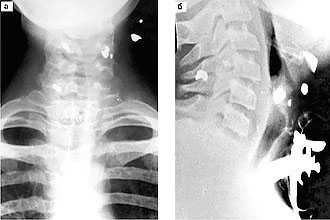

- МСКТ и рентгенография гортани;

Периферические парезы и параличи гортани выявляются посредством проведения КТ и обзорной рентгенографии грудной клетки, ультразвукового исследования щитовидной железы, КТ щитовидной железы, ультразвукового исследования сердца, рентгенографии пищевода.

- рентгенография и компьютерная томография, в том числе с контрастированием, полезные для выявления опухолей, стенозов, пороков развития;

В диагностике используется рентгенография, где обнаруживаются признаки мелкоочаговой пневмонии. При пальпации живота выявляется спленомегалия. Картина ларингоскопии представлена глубокими болезненными язвенными дефектами, которые нарушают глотание. Подтверждение диагноза проводится на основании серологического, микроскопического и бактериологического исследований.

Травмы гортани диагностируются на основании результатов рентгенологического, ларингоскопического исследования, УЗИ и компьютерной томографии.